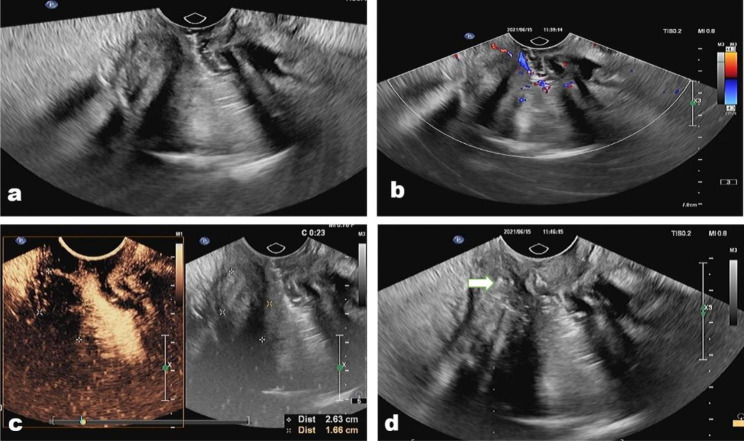

Fig. 2.

(a) An inflammatory lesion located in the medium rectum in a 46-year-old man. (b) The lesion showed an absence of vascularity in the lesion but abundant vascularity in the peripheral tissue on color Doppler image; (c) the lesion presented non-enhanced on contrast-enhanced condition; (d) The biopsy needle (arrow) pass from the basal of the lesion to acquire biopsy samples both from the lesion and peripheral tissue